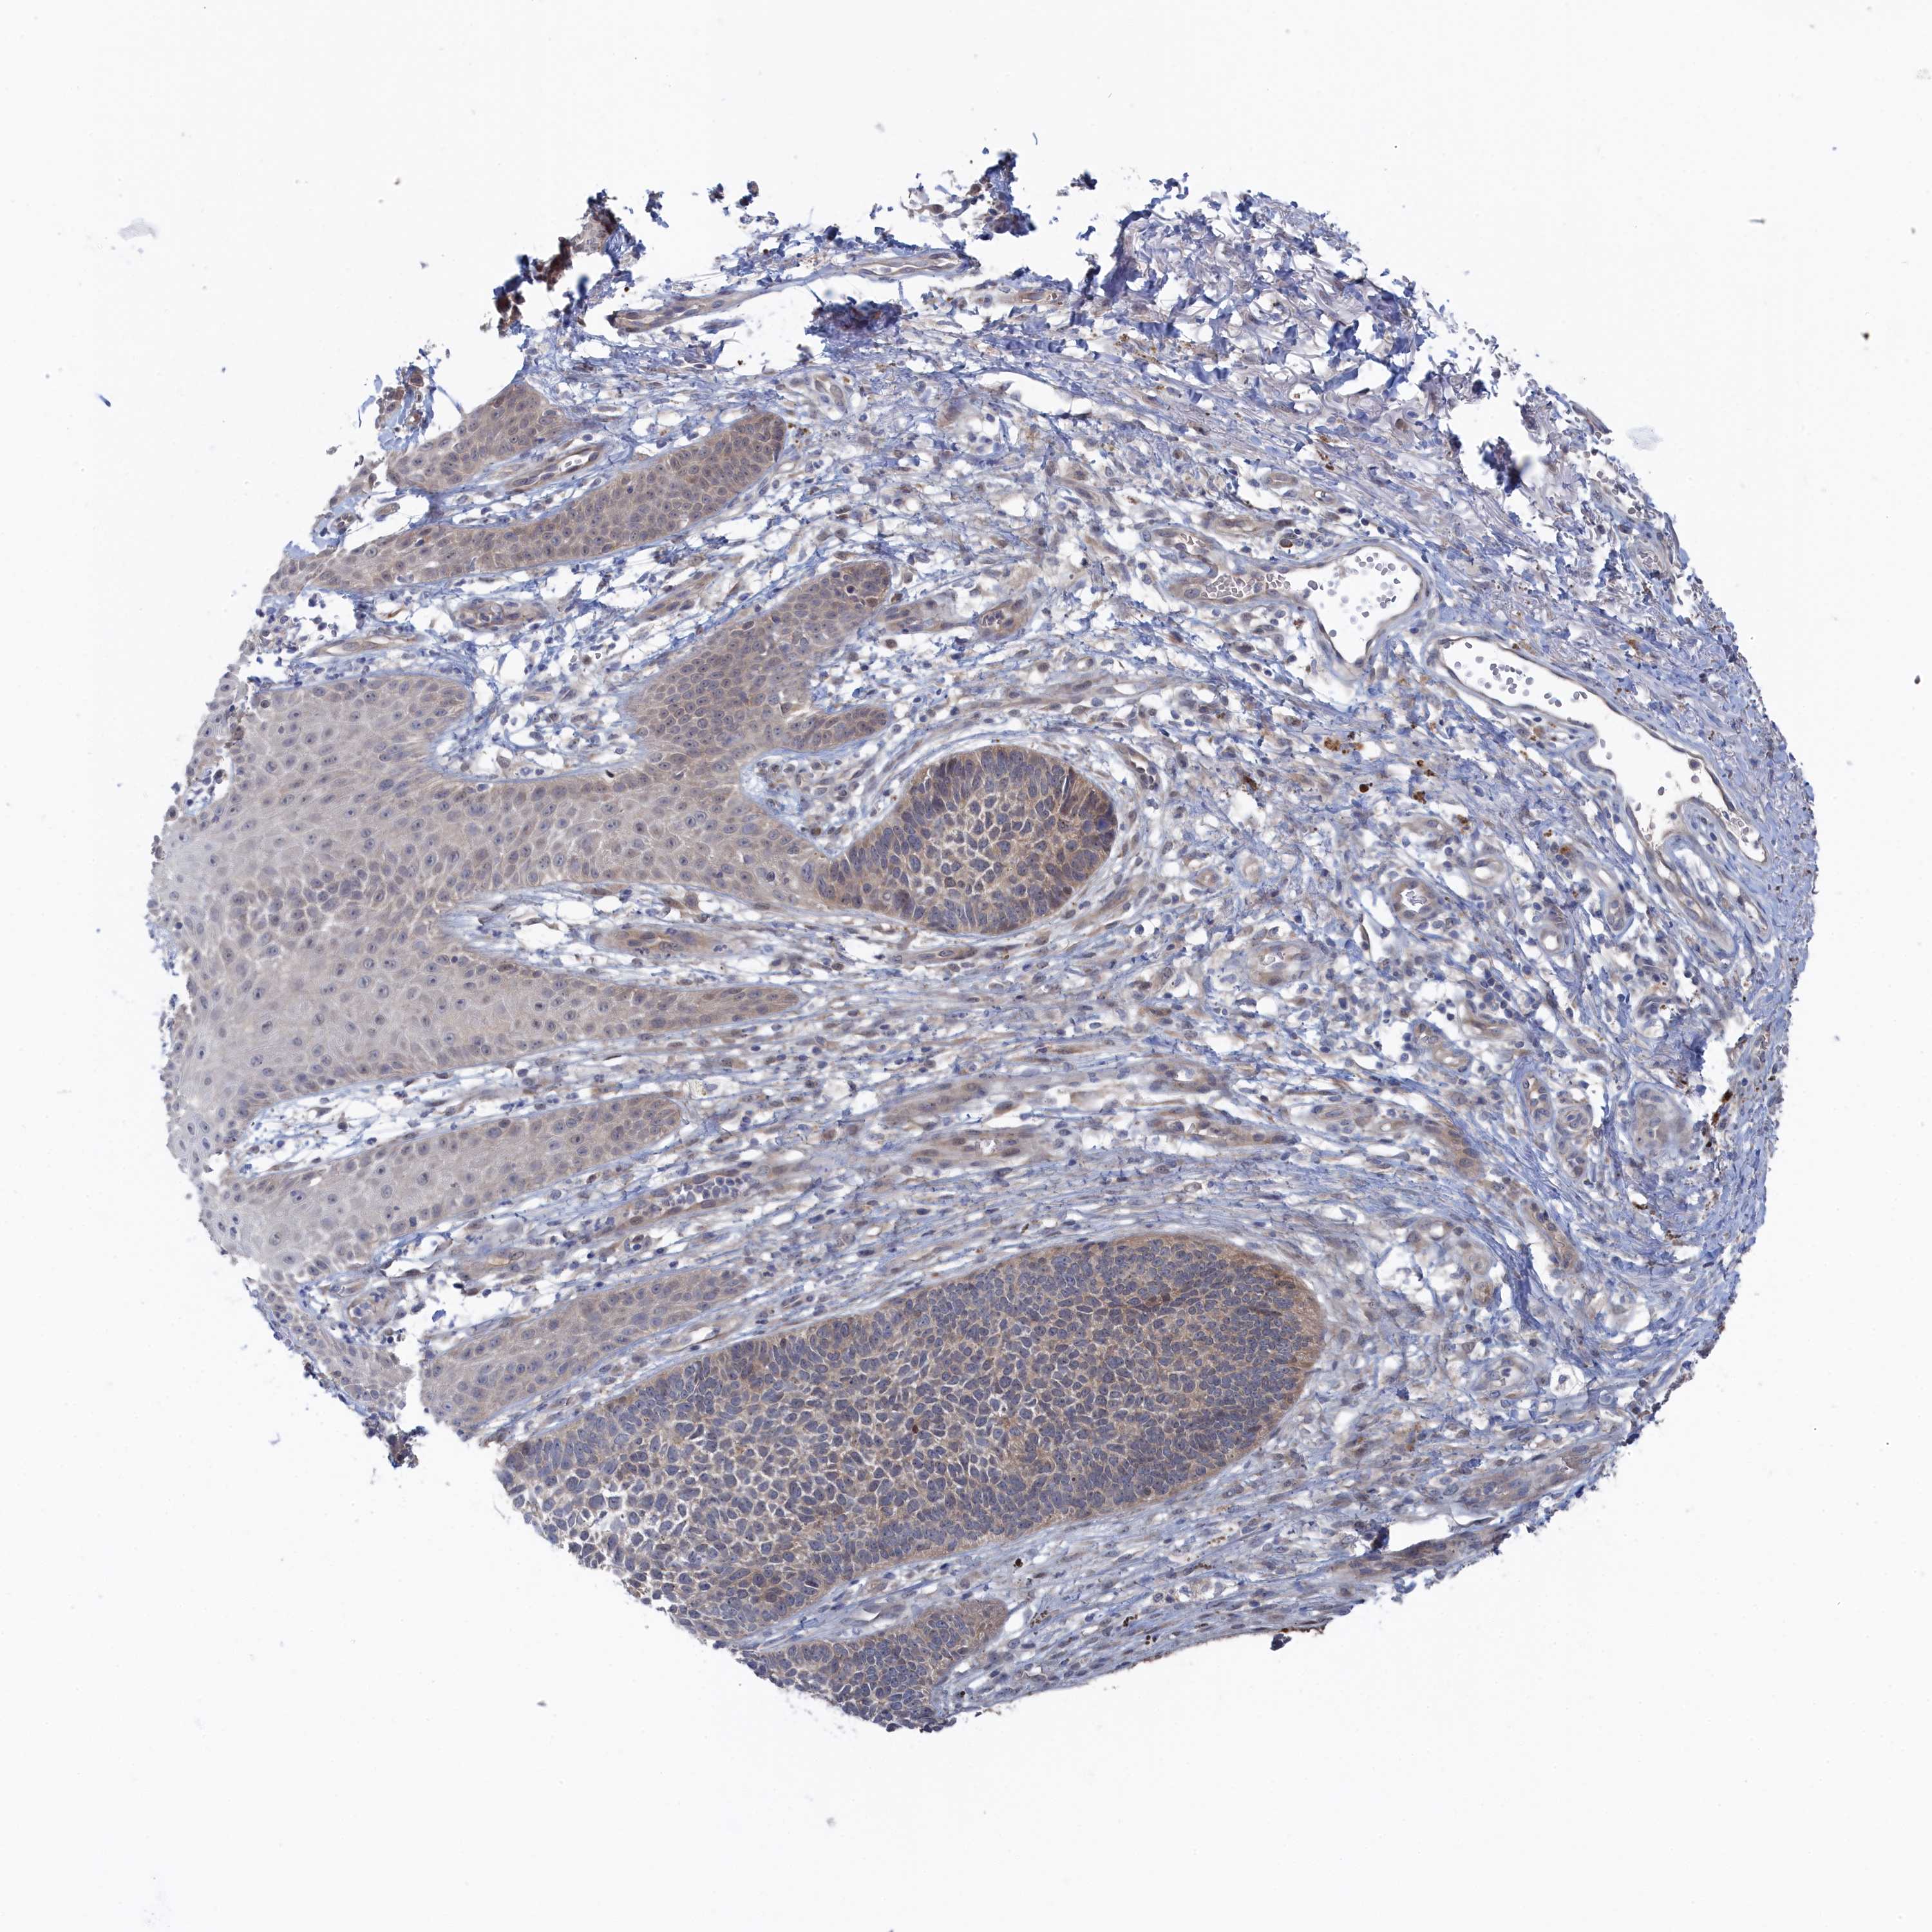

SKIN CANCER - Protein expressioni

A mouse-over function shows sample information and annotation data. Click on an image to view it in a full screen mode. Samples can be filtered based on level of antibody staining by selecting one or several of the following categories: high, medium, low and not detected. The assay and annotation is described here.

Antibody stainingi

Antibody staining in the annotated cell types in the current human tissue is reported as not detected, low, medium, or high, based on conventional immunohistochemistry profiling in selected tissues. This score is based on the combination of the staining intensity and fraction of stained cells.

Each image is clickable and will lead to virtual microscopy that enables deeper exploration of all samples and also displays staining intensity scores, fraction scores and subcellular localization as well as patient and tissue information for each sample.

Antibody HPA043254

Staining

High

Medium

Low

Not detected

Intensity

Strong

Moderate

Weak

Negative

Quantity

>75%

75%-25%

<25%

None

Location

Nuclear

Cytoplasmic/membranous

Cytoplasmic/membranous,nuclear

Basal cell carcinoma